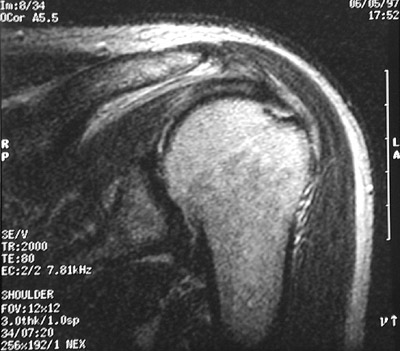

| Tendinitis or injury of the rotator cuff is often the cause for shoulder pain. The supraspinatus tendon is most often affected. There can be inflammation, fibrosis and adjacent bursitis. The supraspinatus tendon can be torn by falling on an outstretched arm or lifting a heavy object. Seen here is an MRI scan of the left shoulder demonstrating a full thickness tear of the supraspinatus tendon. |